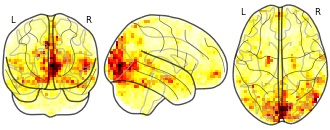

Movie clips: importance map LRP 3 Happiness

EmailClick to copy linkLink copied Cite(2018). Movie clips: importance map LRP 3 Happiness [Dataset]. http://identifiers.org/neurovault.image:58827niftiAvailable download formatsUnique identifierhttps://identifiers.org/neurovault.image:58827Dataset updatedJan 9, 2018License

Movie clips: Reproducibility map LRP p0.010 3 Happiness

EmailClick to copy linkLink copied Cite(2018). Movie clips: Reproducibility map LRP p0.010 3 Happiness [Dataset]. http://identifiers.org/neurovault.image:58801niftiAvailable download formatsUnique identifierhttps://identifiers.org/neurovault.image:58801Dataset updatedJan 9, 2018License